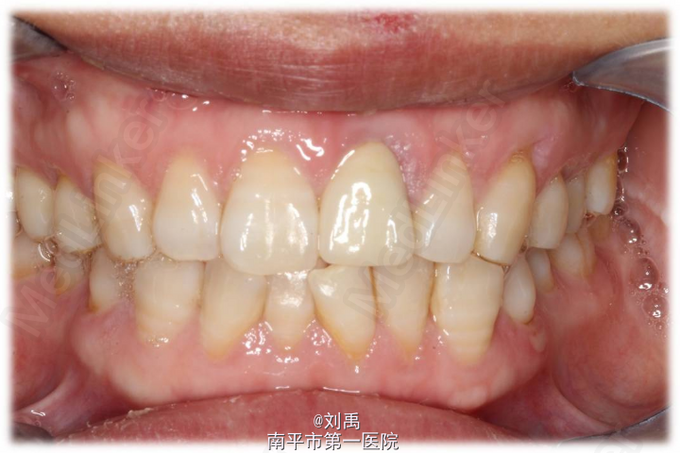

主诉:前牙缺损,要求修复 现病史:患者两月前左上前牙缺损,于我院行牙体治疗,近来我科要求修复。

21牙根管内可见充填物,根尖周无明显异常。

诊断:残冠 切龈后,预备桩道,植入纤维桩,牙体预备,比色,戴暂冠,复诊戴牙